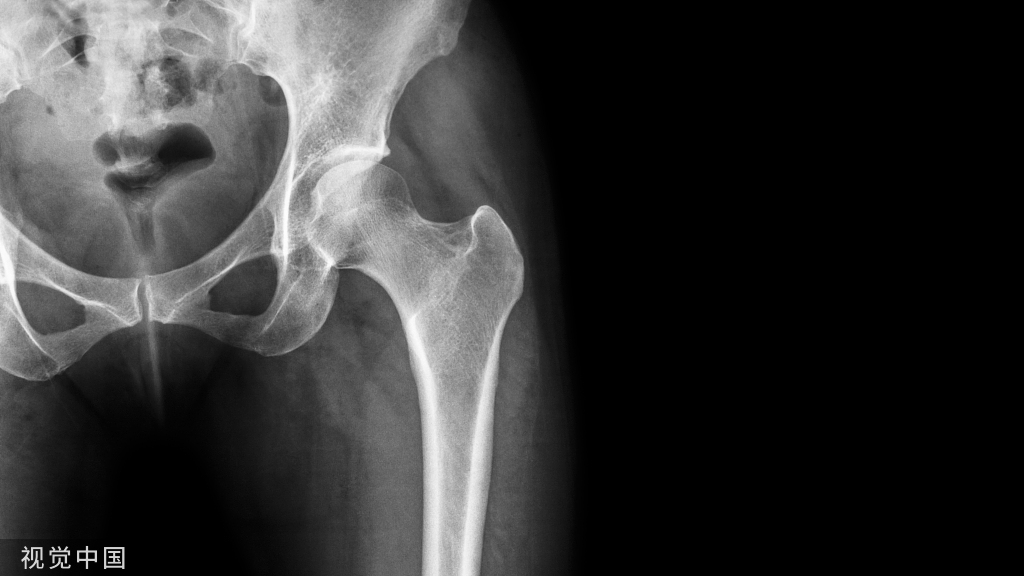

植入生物型股骨柄前,到底要不要冲洗股骨髓腔?

我们知道在植入骨水泥型股骨柄前,要冲洗髓腔,以除去髓腔内碎骨块及血凝块,清洁骨床,使骨水泥-骨界面获得最佳的微交锁稳定。但是,生物型股骨柄在植入之前,是否也应该增加这一髓腔冲洗程序,相关研究较少,是否有益处,目前还不清楚。

40例患者,随机分为两组:髓腔冲洗组(20例)和非冲洗组(20例)。假体均采用CLS股骨柄(Zimmer, USA)。重点测试假体植入后的稳定性,即采用放射立体照相测量分析(radiostereometric analysis, SÁ)测量假体下沉及前倾角的变化情况(测试时间点分别为术后3、12、24、72个月)

研究显示,两组在术后3、12、24、72个月等时间点上,假体下沉及旋转移位均无统计学上的差异,但冲洗组,移位值相对较高。随访6年,两组均无患者因股骨柄松动而翻修。

冲洗髓腔不影响假体稳定性,也没有任何益处。

生物型股骨柄植入前,不要冲洗髓腔。其可能的优点之一,是将扩髓残留碎骨保存在髓腔内,避免冲洗对松质骨进一步损伤,有利于保存骨量;之二,是保存骨髓内潜在的促成骨生长因子。